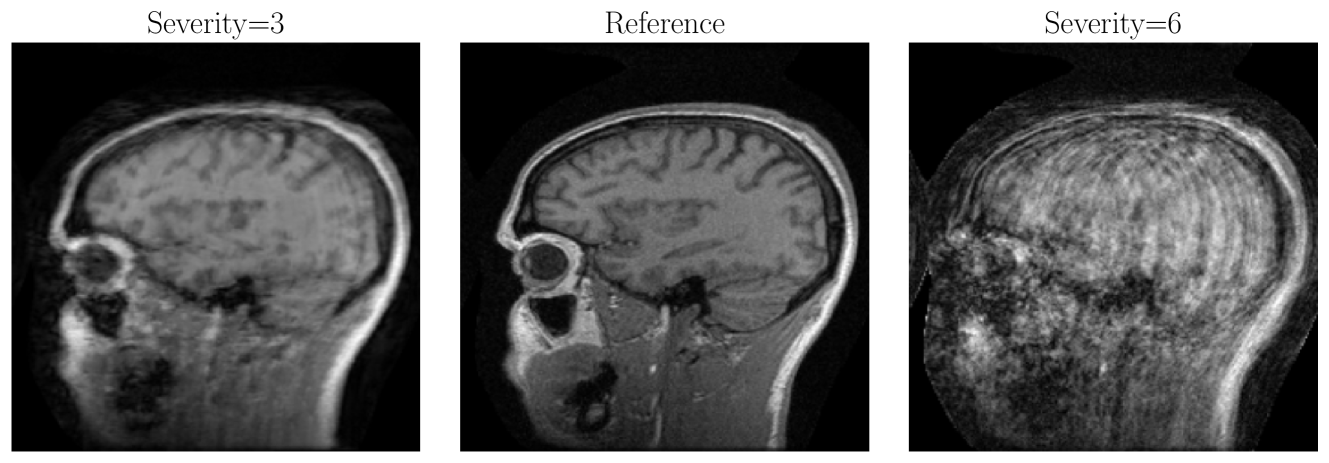

Figure 1: Sagittal views and corresponding perceived motion artifact scores (PMAS) of selected L1-reconstructions from our dataset with varying degrees of motion artifacts ranging from mild (S7_1, S5_1) to moderate S6_2) to severe (S8_2, S2_1). These examples highlight the challenges in reconstructing motion-corrupted scans.

Figure 1 shows sagittal views of L1-reconstructions from our dataset from left to right in ascending order according to their perceived motion artifact score. As we can see, the severity of motion artifacts increases with increasing perceived motion artifact score. Reconstructions S7_3 and S5_2 show mild artifacts, where most brain anatomical details are preserved despite the presence of minor ringing artifacts. In reconstruction S6_2, the artifacts are more pronounced and obscure finer details, while in S8_2 and S2_1 the artifacts are severe enough that the brain structures become barely discernible. These examples illustrate the range of challenges encountered when reconstructing motion-corrupted scans in our dataset.